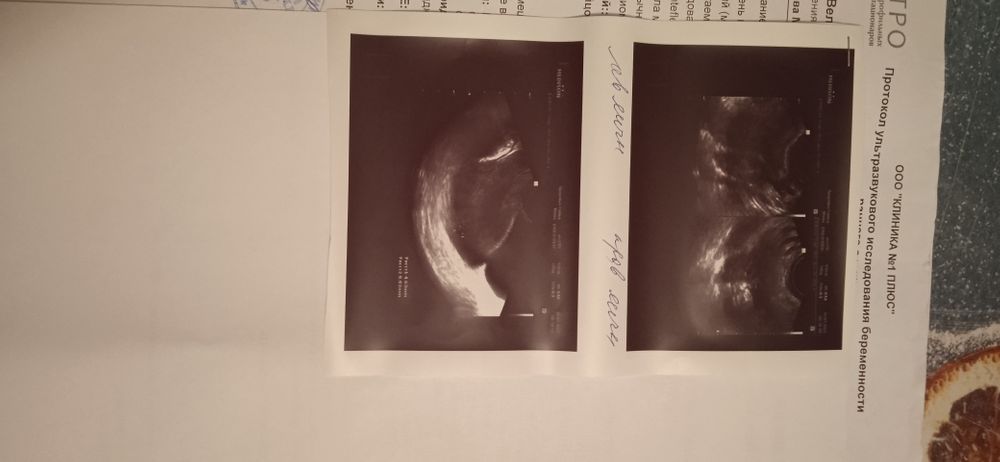

Назначили ДЮФАСТОН, МАГНЕЛИС Б6 И ТРАКСИПАМ. СКАЖИТЕ ПОЖАЛУЙСТА, НОРМАЛИ ЛИ ЧТО ЖМ НЕ ОПРЕДЕЛЯЕТЬСЯ И ЭМБРИОН?

Желтое тело есть, плодное яйцо есть, диаметр плодного яйца хороший, а гематому будут наблюдать, все соответствует сейчас.

Беременность 6-7 недель, что соответсвует вашему сроку по месячным, но возможно есть гематома. За ней надо в динамике следить и обязательно с врачом обсудить это.

Была ретрохориальная гематома..постельный режим...

Переживаю что ребёночка не видно, и так же не понимаю откуда эта гематома могла появиться